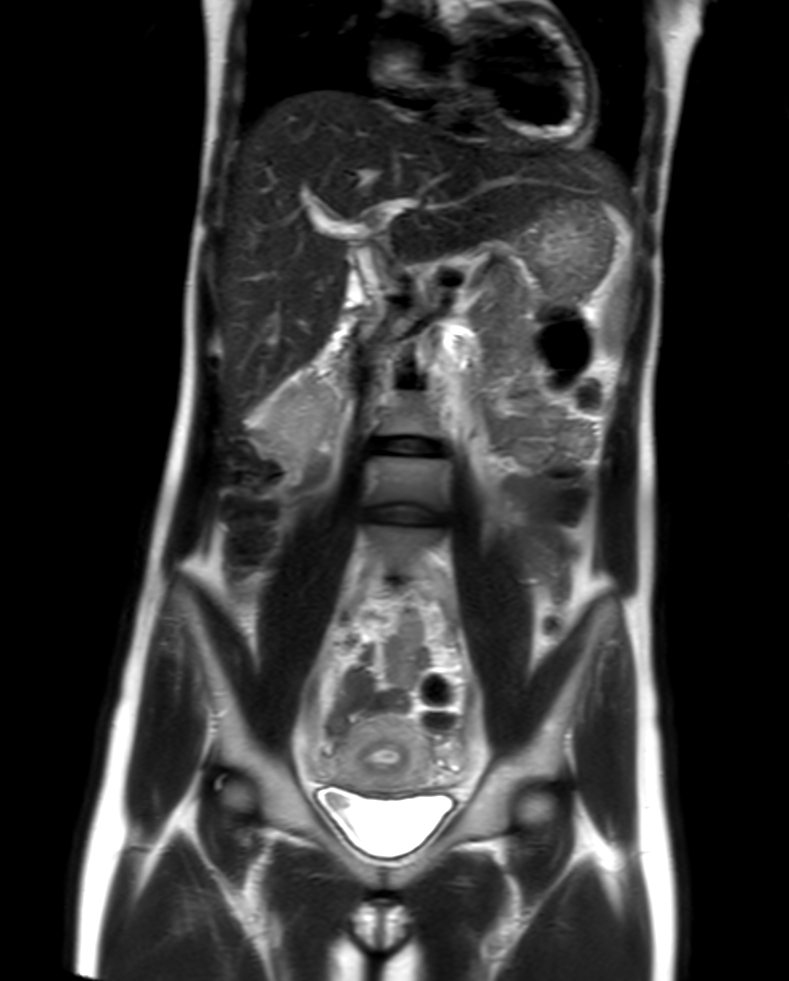

Coronal T2w TSE